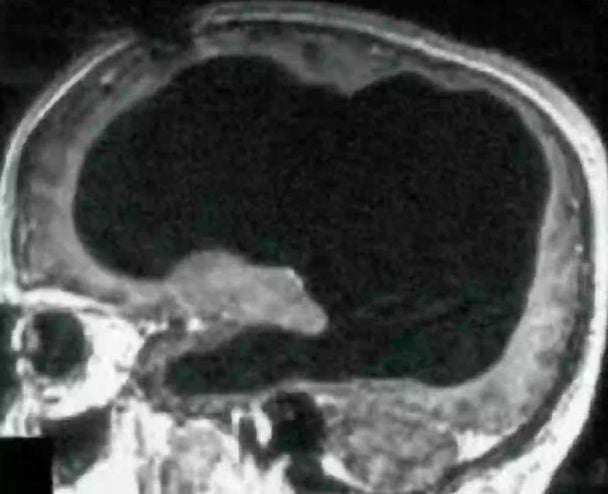

Француз виявив, що живе з половиною мозку. Відкриття поставило в глухий кут вчених, яким довелося переоцінити те, що ми знаємо про мозок і його зв'язок з рештою тіла.

Втім, він дізнався, що у нього не вистачає понад половину мозку. Натомість череп чоловіка був фактично заповнений рідиною, а від мозкової тканини залишився лише тонкий шар. Цей стан навіть має назву – гідроцефалія.

Чоловік прожив усе своє життя, не думаючи, що з ним щось не так. Лікарі вважають, що більша частина його мозку повільно руйнувалася протягом 30 років через накопичення рідини в мозку через його стан.

Цікаво, що йому поставили цей діагноз ще в дитинстві і лікували за допомогою стента, який видалили, коли йому було 14 років, і відтоді більша частина його мозку, схоже, була розмита.